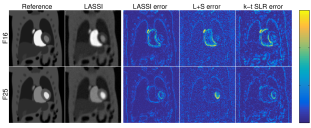

Fig. 3 shows the NRMSE values computed between each reconstructed and reference frame for the LASSI, L+S, and k-t SLR outputs for two datasets. The proposed LASSI scheme clearly outperforms the previous L+S and k-t SLR methods across frames (time). Fig. 4 shows the LASSI reconstructions of some representative frames (the supplement shows more such reconstructions) for each dataset in Tables I-III. The reconstructed frames are visually similar to the reference frames (fully sampled reconstructions) shown. Fig. 4 also shows the reconstruction error maps (i.e., the magnitude of the difference between the magnitudes of the reconstructed and reference frames) for LASSI, L+S, and k-t SLR for the representative frames of each dataset. The error maps for LASSI show fewer artifacts and smaller distortions than the other methods. Results included in the supplement show that LASSI recovers temporal () profiles in the dynamic data with greater fidelity than other methods.

Figs. 2(g) and (h) show the reconstructions777Gamma correction was used to better display the images in this work. and and components of two representative frames produced by the L+S [45] (with parameters optimized to achieve best NRMSE) and LASSI (OPT update and sparsity) methods, respectively. The LASSI reconstructions are sharper and a better approximation of the reference frames (fully sampled reconstructions) shown. In particular, the component of the LASSI reconstruction is clearly low-rank, and the component captures the changes in contrast and other dynamic features in the data. On the other hand, the component of the conventional L+S reconstruction varies more over time (i.e., it has higher rank), and the component contains relatively little information. The richer decomposition produced by LASSI suggests that both the low-rank and adaptive dictionary-sparse components of the model are well-suited for dMRI.